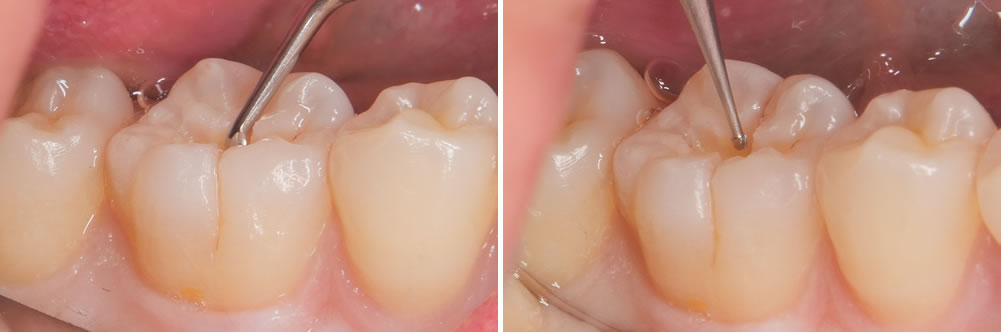

右下の奥歯に黒い部分が見受けられます。範囲は小さいため、出来るだけ削らないように先端の小さな器具を用いて丁寧に虫歯を除去していきます。

虫歯治療の除去

う蝕検知液を用いて丁寧に虫歯を取り除いていきます。

さらに奥にある虫歯は、より小さな器具を用いて削る範囲が大きくなりすぎないようにします。